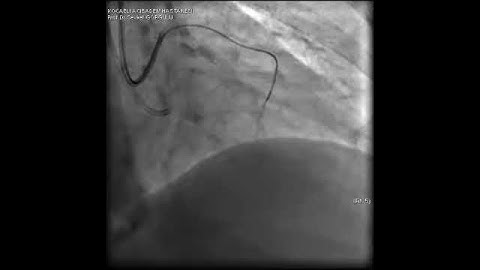

Aortic dissection and radial rupture during retrograde CTO PCI: Management of complications VİDEO 7